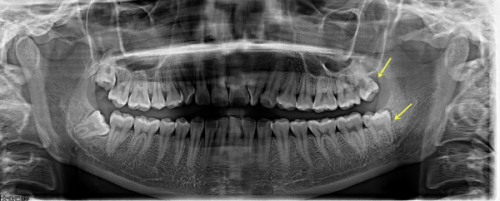

设备设施上,医院配备了精良的口腔CT、数字化口扫仪等设备。这些设备能够为医生提供正确的诊断依据,提高治疗的精细度。例如,数字化口扫仪可以快速获取患者口腔的三维模型,让医生更直观地了解患者的口腔情况,制定更合适的治疗方案。